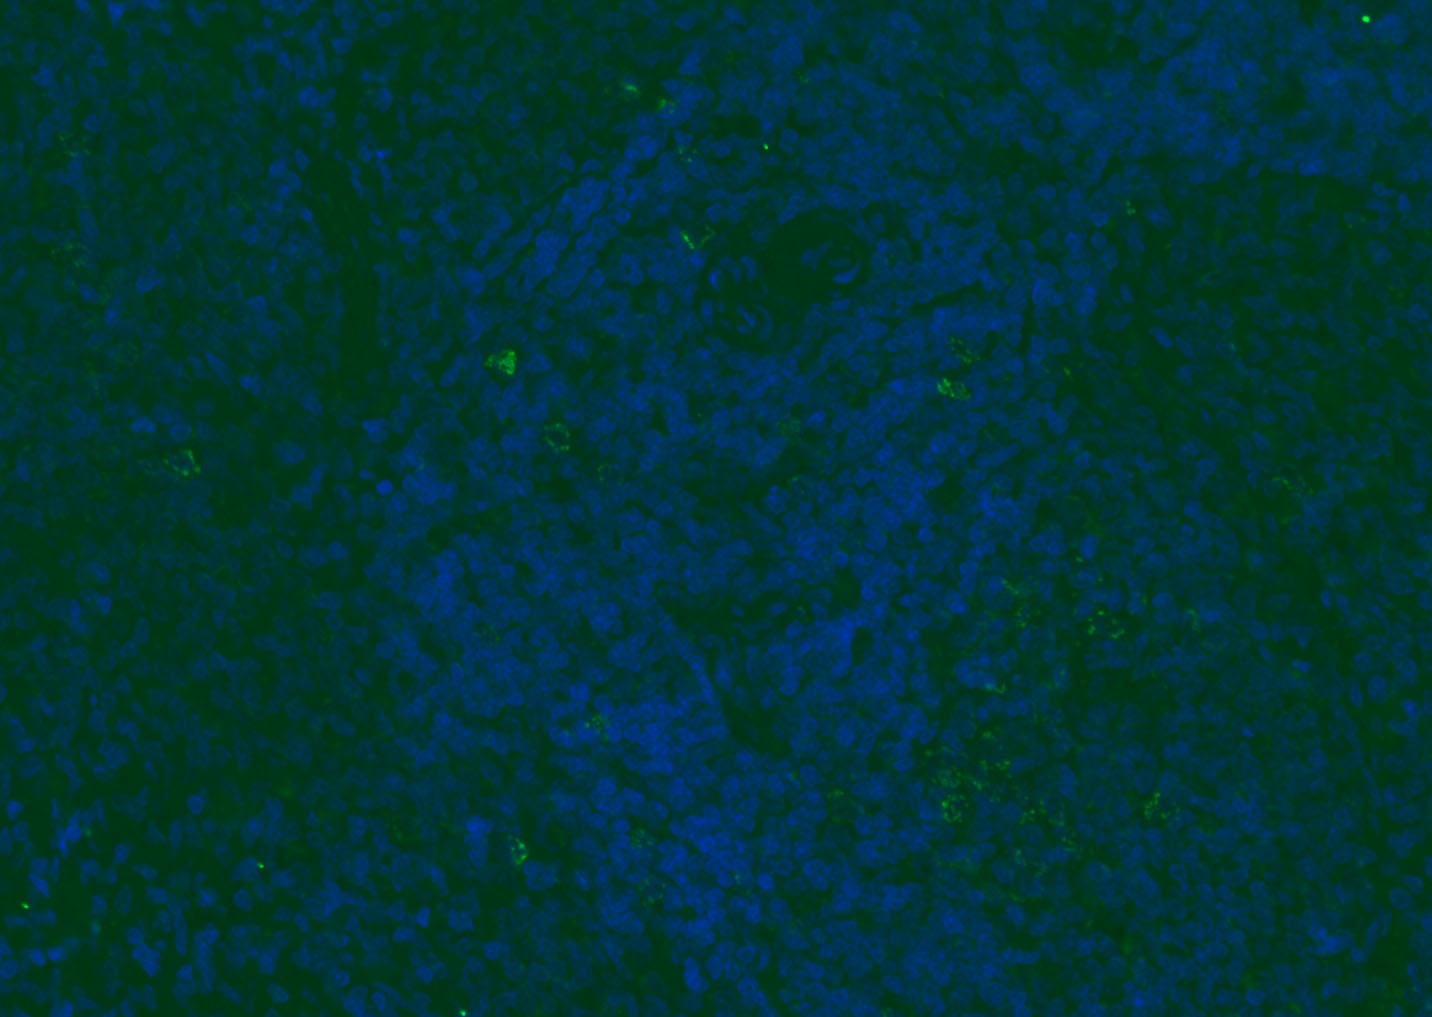

| Verified Activity | 1. Tissue/cell: human lung carcinoma;4% Paraformaldehyde-fixed and paraffin-embedded; Antigen retrieval: citrate buffer (0.01M, pH6.0), Boiling bathing for 15 min; Blocking buffer (normal goat serum) at 37°C for 20 min; Incubation: Anti-CD8 Polyclonal Antibody, Unconjugated (TMAB-00392) 1:200, overnight at 4°C; The secondary antibody was Goat Anti-Rabbit IgG, Cy3 conjugated used at 1:200 dilution for 40 minutes at 37°C. DAPI (5 μg/ml,blue) was used to stain the cell nucleus. 2. Paraformaldehyde-fixed, paraffin embedded (mouse lymphoid); Antigen retrieval by boiling in sodium citrate buffer (pH6.0) for 15 min; Blocking buffer (normal goat serum) at 37°C for 30 min; Antibody incubation with (CD8B) Polyclonal Antibody, Unconjugated (TMAB-00392) at 1:200 overnight at 4°C, followed by a conjugated Goat Anti-Rabbit IgG antibody for 90 minutes, and DAPI for nucleus staining. 3. Paraformaldehyde-fixed, paraffin embedded (rat spleen); Antigen retrieval by boiling in sodium citrate buffer (pH6.0) for 15 min; Blocking buffer (normal goat serum) at 37°C for 30 min; Antibody incubation with (CD8B) Polyclonal Antibody, Unconjugated (TMAB-00392) at 1:200 overnight at 4°C, followed by a conjugated Goat Anti-Rabbit IgG antibody for 90 minutes, and DAPI for nucleus staining. 4. Paraformaldehyde-fixed, paraffin embedded (mouse thymus); Antigen retrieval by boiling in sodium citrate buffer (pH6.0) for 15 min; Blocking buffer (normal goat serum) at 37°C for 30 min; Antibody incubation with (CD8B) Polyclonal Antibody, Unconjugated (TMAB-00392) at 1:200 overnight at 4°C, followed by a conjugated Goat Anti-Rabbit IgG antibody for 90 minutes, and DAPI for nucleus staining. 5. Paraformaldehyde-fixed, paraffin embedded (rat lymphoid); Antigen retrieval by boiling in sodium citrate buffer (pH6.0) for 15 min; Blocking buffer (normal goat serum) at 37°C for 30 min; Antibody incubation with (CD8B) Polyclonal Antibody, Unconjugated (TMAB-00392) at 1:200 overnight at 4°C, followed by a conjugated Goat Anti-Rabbit IgG antibody for 90 minutes, and DAPI for nucleus staining. 6. Paraformaldehyde-fixed, paraffin embedded (rat thymus); Antigen retrieval by boiling in sodium citrate buffer (pH6.0) for 15 min; Blocking buffer (normal goat serum) at 37°C for 30 min; Antibody incubation with (CD8B) Polyclonal Antibody, Unconjugated (TMAB-00392) at 1:200 overnight at 4°C, followed by a conjugated Goat Anti-Rabbit IgG antibody for 90 minutes, and DAPI for nucleus staining. 7. Paraformaldehyde-fixed, paraffin embedded (human tonsil); Antigen retrieval by boiling in sodium citrate buffer (pH6.0) for 15 min; Blocking buffer (normal goat serum) at 37°C for 30 min; Antibody incubation with (CD8B) Polyclonal Antibody, Unconjugated (TMAB-00392) at 1:200 overnight at 4°C, followed by a conjugated Goat Anti-Rabbit IgG antibody for 90 minutes, and DAPI for nucleus staining. 8. Paraformaldehyde-fixed, paraffin embedded (mouse lymphoid); Antigen retrieval by boiling in sodium citrate buffer (pH6.0) for 15 min; Blocking buffer (normal goat serum) at 37°C for 30 min; Antibody incubation with (CD8B) Polyclonal Antibody, Unconjugated (TMAB-00392) at 1:200 overnight at 4°C, followed by a conjugated Goat Anti-Rabbit IgG antibody for 90 minutes, and DAPI for nucleus staining. 9. Paraformaldehyde-fixed, paraffin embedded (rat thymus); Antigen retrieval by boiling in sodium citrate buffer (pH6.0) for 15 min; Blocking buffer (normal goat serum) at 37°C for 30 min; Antibody incubation with (CD8B) Polyclonal Antibody, Unconjugated (TMAB-00392) at 1:200 overnight at 4°C, followed by a conjugated Goat Anti-Rabbit IgG antibody for 90 minutes, and DAPI for nucleus staining. 10. Paraformaldehyde-fixed, paraffin embedded (human tonsil); Antigen retrieval by boiling in sodium citrate buffer (pH6.0) for 15 min; Blocking buffer (normal goat serum) at 37°C for 30 min; Antibody incubation with (CD8B) Polyclonal Antibody, Unconjugated (TMAB-00392) at 1:200 overnight at 4°C, followed by a conjugated Goat Anti-Rabbit IgG antibody for 90 minutes, and DAPI for nucleus staining. 11. Paraformaldehyde-fixed, paraffin embedded (mouse spleen); Antigen retrieval by boiling in sodium citrate buffer (pH6.0) for 15 min; Blocking buffer (normal goat serum) at 37°C for 30 min; Antibody incubation with (CD8B) Polyclonal Antibody, Unconjugated (TMAB-00392) at 1:200 overnight at 4°C, followed by a conjugated Goat Anti-Rabbit IgG antibody for 90 minutes, and DAPI for nucleus staining. 12. Paraformaldehyde-fixed, paraffin embedded (rat lymphoid); Antigen retrieval by boiling in sodium citrate buffer (pH6.0) for 15 min; Blocking buffer (normal goat serum) at 37°C for 30 min; Antibody incubation with (CD8B) Polyclonal Antibody, Unconjugated (TMAB-00392) at 1:200 overnight at 4°C, followed by a conjugated Goat Anti-Rabbit IgG antibody for 90 minutes, and DAPI for nucleus staining. 13. Paraformaldehyde-fixed, paraffin embedded (Rat lymphoid); Antigen retrieval by boiling in sodium citrate buffer (pH6.0) for 15 min; Blocking buffer (normal goat serum) at 37°C for 30 min; Antibody incubation with (CD8B) Polyclonal Antibody, Unconjugated (TMAB-00392) at 1:100 overnight at 4°C, followed by a conjugated Goat Anti-Rabbit IgG antibody for 90 minutes, and DAPI for nucleus staining. 14. Paraformaldehyde-fixed, paraffin embedded (mouse thymus); Antigen retrieval by boiling in sodium citrate buffer (pH6.0) for 15 min; Blocking buffer (normal goat serum) at 37°C for 30 min; Antibody incubation with (CD8B) Polyclonal Antibody, Unconjugated (TMAB-00392) at 1:100 overnight at 4°C, followed by a conjugated Goat Anti-Rabbit IgG antibody for 90 minutes, and DAPI for nucleus staining. 15. Paraformaldehyde-fixed, paraffin embedded (mouse spleen); Antigen retrieval by boiling in sodium citrate buffer (pH6.0) for 15 min; Blocking buffer (normal goat serum) at 37°C for 30 min; Antibody incubation with (CD8B) Polyclonal Antibody, Unconjugated (TMAB-00392) at 1:100 overnight at 4°C, followed by a conjugated Goat Anti-Rabbit IgG antibody for 90 minutes, and DAPI for nucleus staining. 16. Paraformaldehyde-fixed, paraffin embedded (rat spleen); Antigen retrieval by boiling in sodium citrate buffer (pH6.0) for 15 min; Blocking buffer (normal goat serum) at 37°C for 30 min; Antibody incubation with (CD8B) Polyclonal Antibody, Unconjugated (TMAB-00392) at 1:100 overnight at 4°C, followed by a conjugated Goat Anti-Rabbit IgG antibody for 90 minutes, and DAPI for nucleus staining. 17. Paraformaldehyde-fixed, paraffin embedded (rat thymus); Antigen retrieval by boiling in sodium citrate buffer (pH6.0) for 15 min; Blocking buffer (normal goat serum) at 37°C for 30 min; Antibody incubation with (CD8B) Polyclonal Antibody, Unconjugated (TMAB-00392) at 1:100 overnight at 4°C, followed by a conjugated Goat Anti-Rabbit IgG antibody for 90 minutes, and DAPI for nucleus staining. 18. Paraformaldehyde-fixed, paraffin embedded (human tonsil); Antigen retrieval by boiling in sodium citrate buffer (pH6.0) for 15 min; Blocking buffer (normal goat serum) at 37°C for 30 min; Antibody incubation with (CD8B) Polyclonal Antibody, Unconjugated (TMAB-00392) at 1:100 overnight at 4°C, followed by a conjugated Goat Anti-Rabbit IgG antibody for 90 minutes, and DAPI for nucleus staining. 19. Paraformaldehyde-fixed, paraffin embedded (mouse lymphoid); Antigen retrieval by boiling in sodium citrate buffer (pH6.0) for 15 min; Blocking buffer (normal goat serum) at 37°C for 30 min; Antibody incubation with (CD8B) Polyclonal Antibody, Unconjugated (TMAB-00392) at 1:100 overnight at 4°C, followed by a conjugated Goat Anti-Rabbit IgG antibody for 90 minutes, and DAPI for nucleus staining. ![]() ![]() ![]() ![]() ![]() ![]() ![]() ![]() ![]() ![]() ![]() ![]() ![]() ![]() ![]() ![]() ![]() ![]() ![]() |